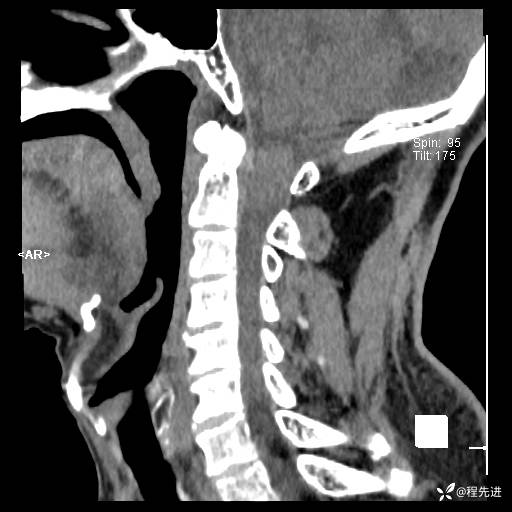

CT平扫: